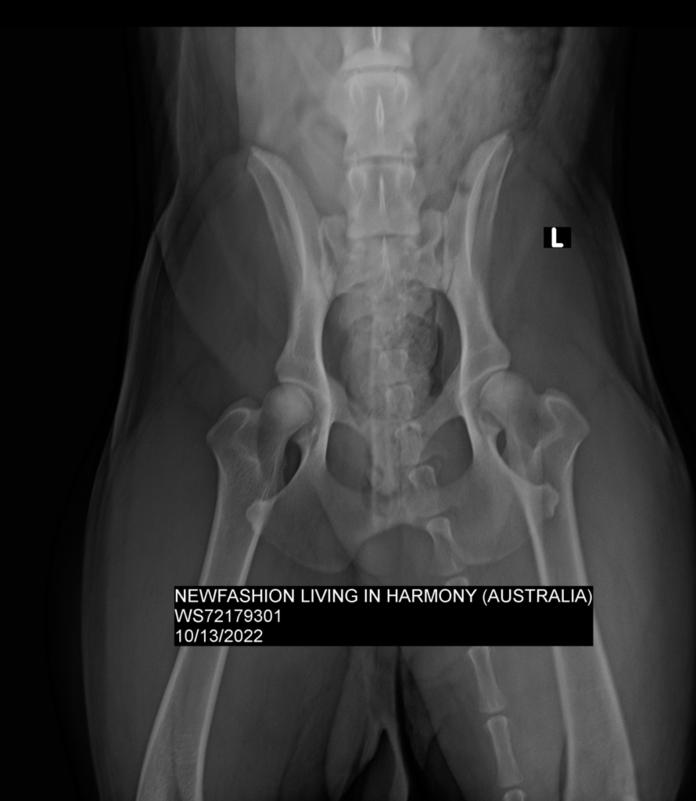

This is Faron's hip xray. OFA rated hip UL dysplasia, but the vet who took the xrays and an independent radiologist both said his hips are good. Both are very experienced with taking and reading hip xrays